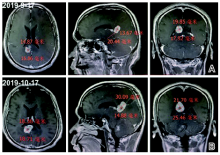

头颅MRI增强扫描+磁共振波谱分析(2019-09-17):胼胝体压部、体部见多发结节状、环状异常信号, 边界清楚, 周围可见大片状水肿信号。考虑脑淋巴瘤(见图1)。

头颅MRI增强扫描(2019-10-17):右侧枕叶病灶活检术后改变, 术区囊腔形成; 右侧胼胝体枕叶占位, 累及对侧、双侧侧脑室、三脑室、右侧桥臂, 病灶较前增大(见图1)。